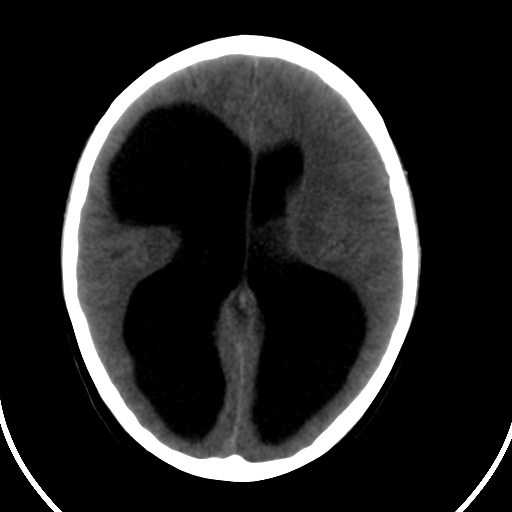

男,11岁

重度脑积水,但第四脑室扩大不明显,考虑导水管阻塞,建议mr。

右额叶单发近圆形低密度影,周边光滑,与侧脑室相通,考虑为孔洞脑并阻塞性脑积水。

右额叶内见一边界清楚,脑脊液密度的囊腔,无灰质内衬,并与脑室相通,四室以上脑室系统高度扩张。诊断:先天性脑穿通畸形伴梗阻性脑积水

需要与脑裂畸形鉴别:可见单侧或双侧衬有皮层的脑裂伸入额顶叶的白质内并与脑室相通

脑穿通畸形并梗阻性脑积水.

脑穿通畸形囊肿脑积水